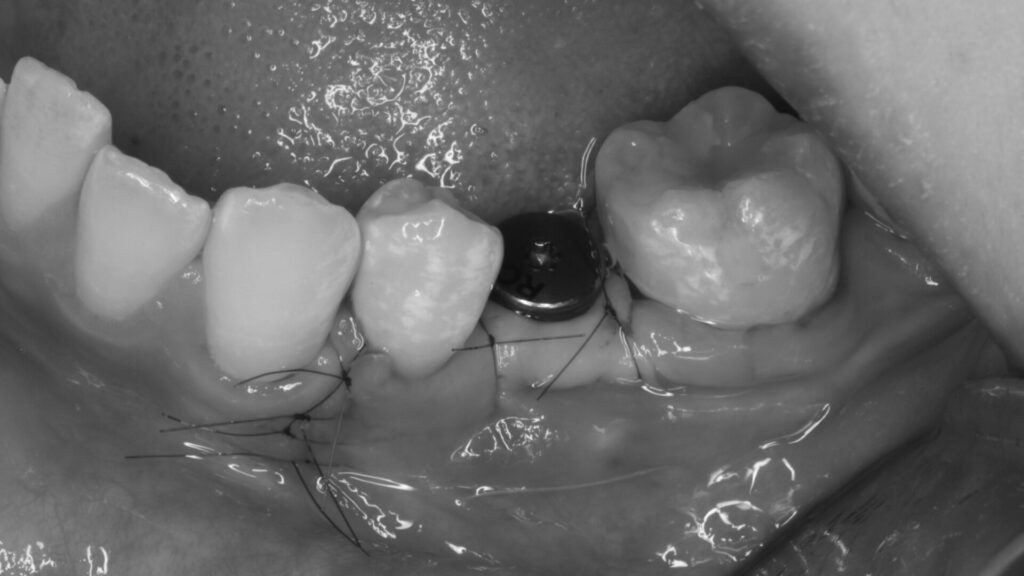

骨造成での対応

今回はインプラント埋め込みと同時に骨補填材量をメインに移植することで骨造成を行いました。外側に骨を増やす骨造成という治療法は術後1週間ほど腫れますが、痛みは最小限で済みました。